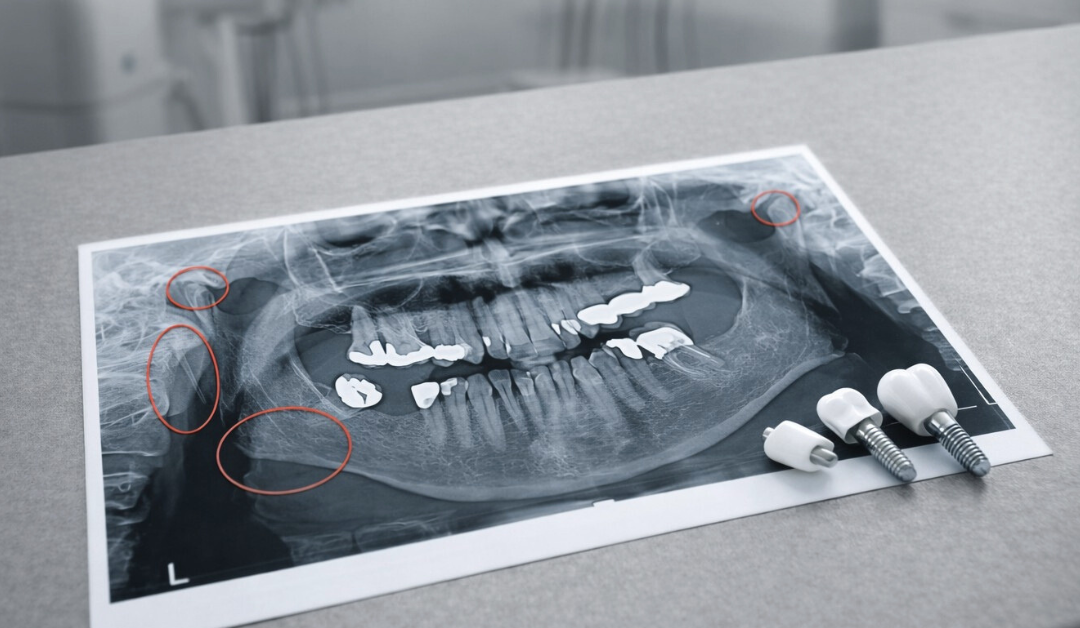

• Radiographic hallmarks such as angular wedge-shaped bone defects that mimic but are distinct from peri-implantitis.

Failing to distinguish mechanical overload from infection-driven bone loss leads to ineffective treatment. While peri-implantitis presents with inflamed tissues, bleeding, and suppuration, occlusal overload often manifests in otherwise healthy soft tissues but shows mechanical failure.